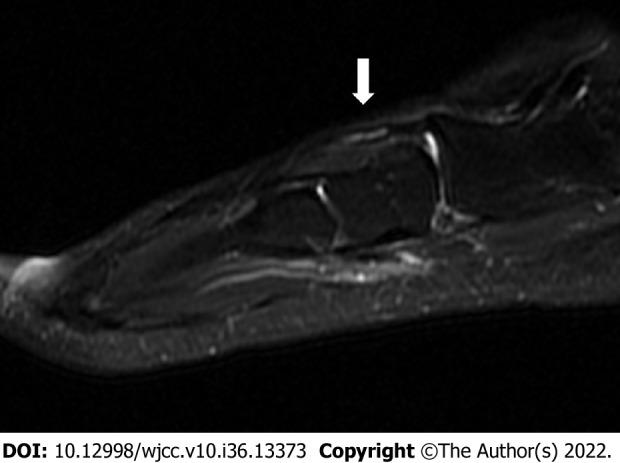

We present the case of a 32-year-old man with an intratendinous ganglion of the second extensor digitorum brevis (EDB) tendon that recurred after ganglion excision. Magnetic resonance imaging (MRI) performed before the first surgery was reviewed to analyze the causes of the recurrence. We confirmed that there was a lack of satellite detection. After recurrence, MRI revealed an extra-tendinous lesion, tenosynovitis, and intratendinous ganglion of the second EDB tendon. Since the second EDB tendon can compensate for the extrinsic muscle, resection was performed alone. In addition, meticulous excision and synovectomy were performed for extra-tendinous lesions and tenosynovitis, respectively. The patient returned to daily life without any functional problems or recurrence.

我们报告一例32岁男性,其第二趾短伸肌腱的腱鞘内腱鞘囊肿在囊肿切除后复发。回顾首次手术前进行的磁共振成像(MRI)以分析复发原因。我们确认存在卫星病灶未被发现的情况。复发后,MRI显示第二趾短伸肌腱有腱外病变、腱鞘炎和腱鞘内腱鞘囊肿。由于第二趾短伸肌腱可代偿外在肌,故单独进行了切除。此外,分别对腱外病变和腱鞘炎进行了细致的切除和滑膜切除术。患者恢复了日常生活,无任何功能问题或复发。